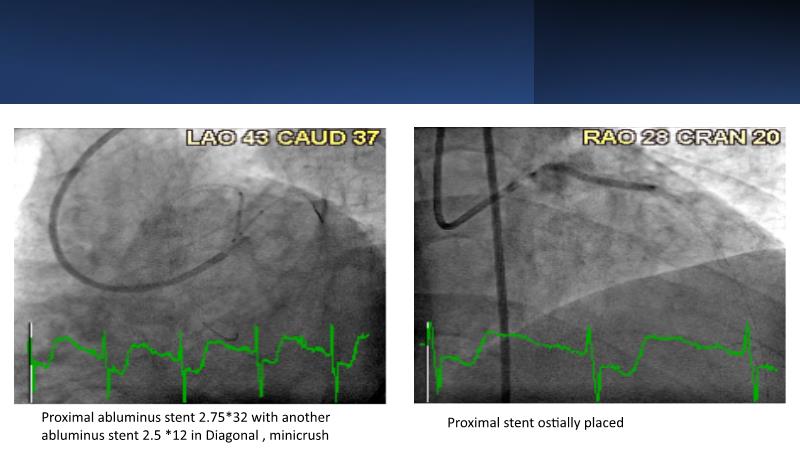

• To know why and how a fusion coating of DES+DCB stent platform is effective for the treatment of cardiovascular disease in diabetes mellitus patients via case presentations

• To understand why you can count on customised drug delivery platform of DES+DCB in complex settings with imaging-based evidence through case presentations